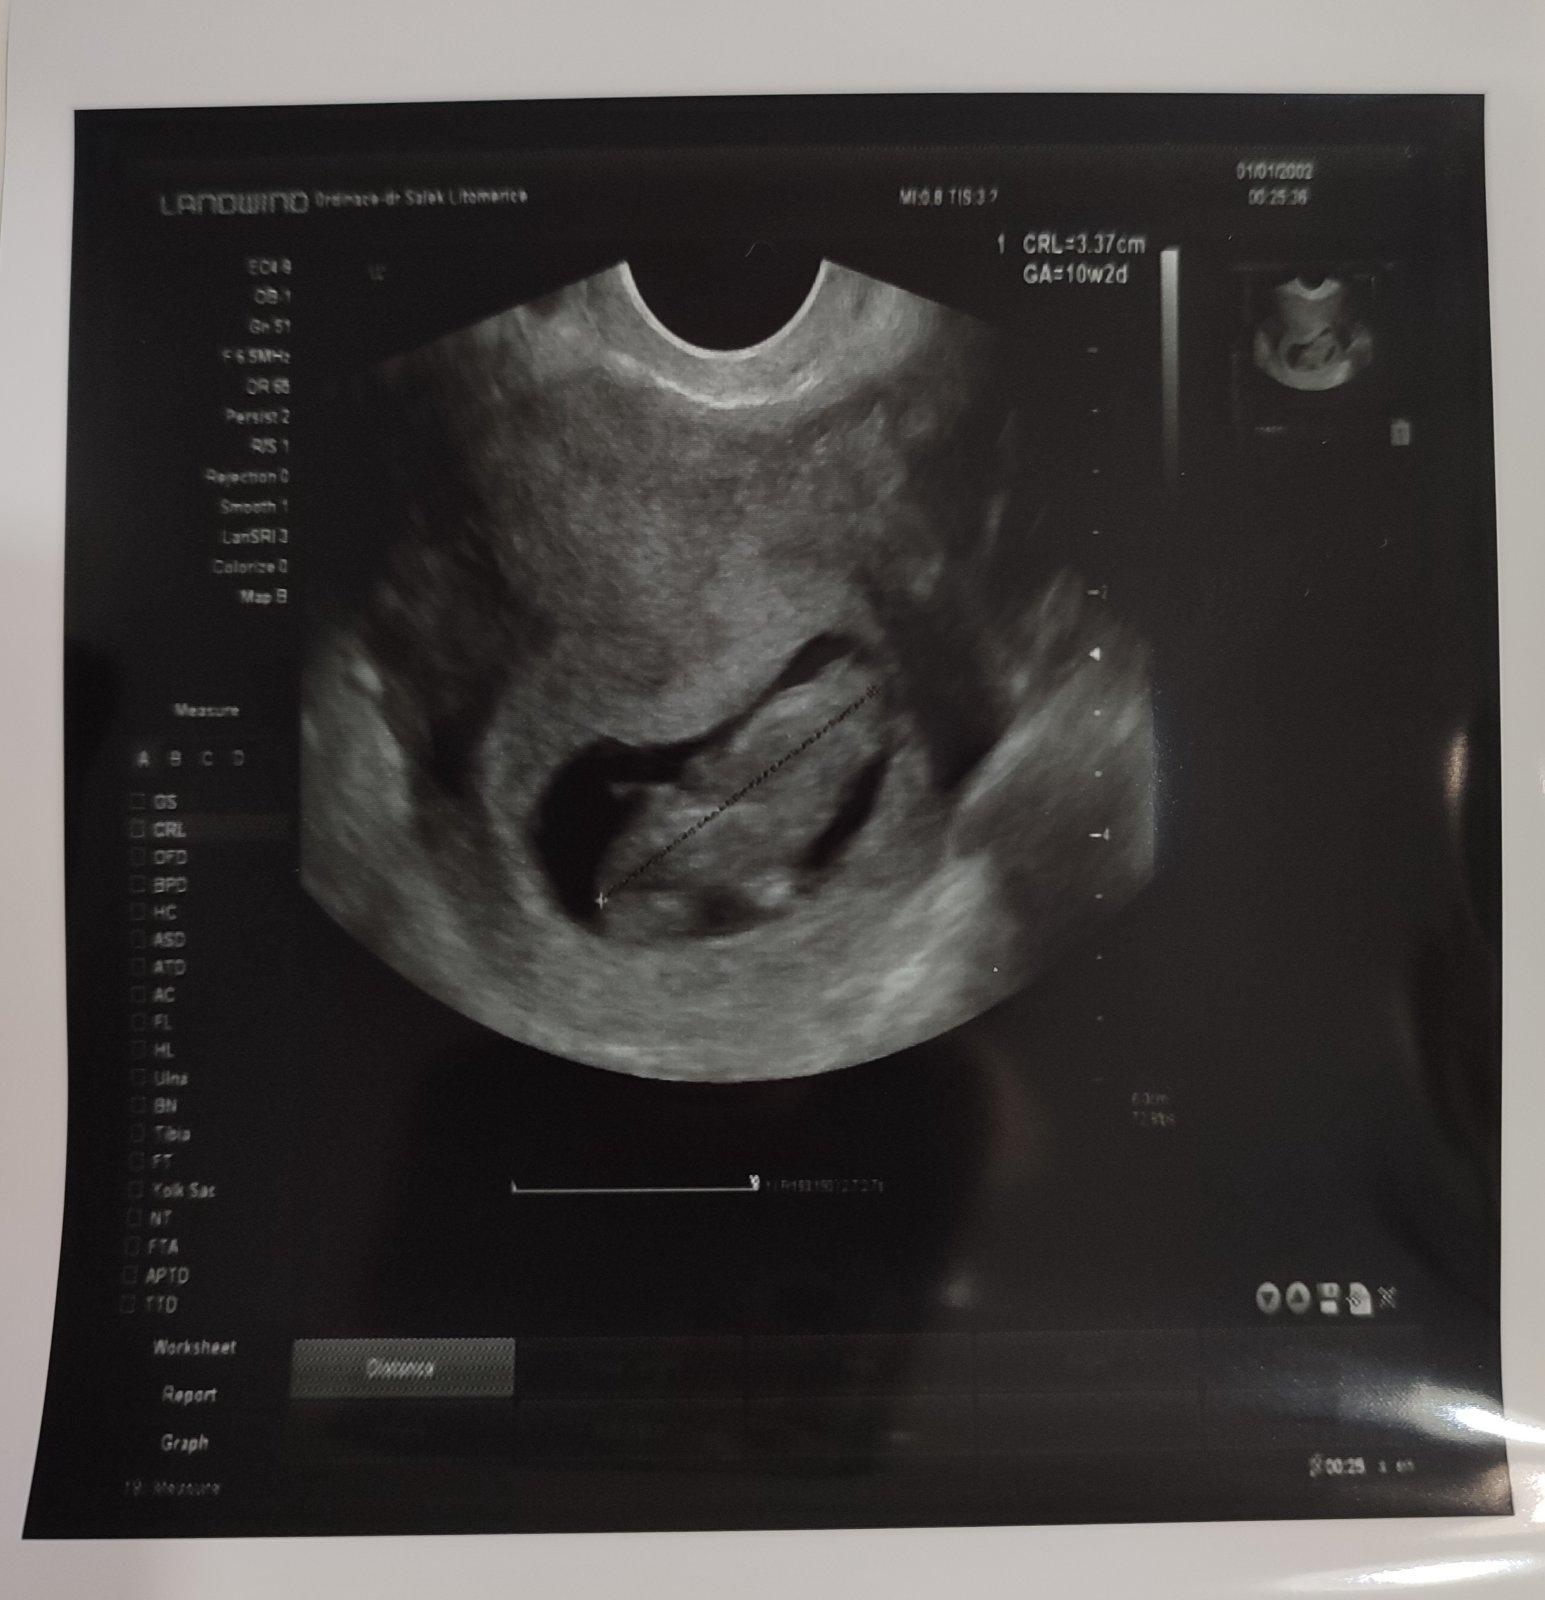

U nás vše v pořádku, po tom jednom krvácení se už další neobjevilo. Na kontrole jsem byla ve čtvrtek a v úterý znovu... už pro průkazku 🙏 a 22.12. první screening.

@majina moc gratuluju a jssem rada, ze je všechno v pořádku,holky po kontrolách pochlubte se s foteckama 🥰já si tady kratim čas vasema fazolkama do další kontroly a to až do 19.12 🙈😄